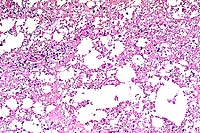

4x

obj.

- Case 22-1. Lung. Exudate fills an ulcerated bronchus

and extends into the surrounding parenchyma, obscuring normal

alveolar architecture.